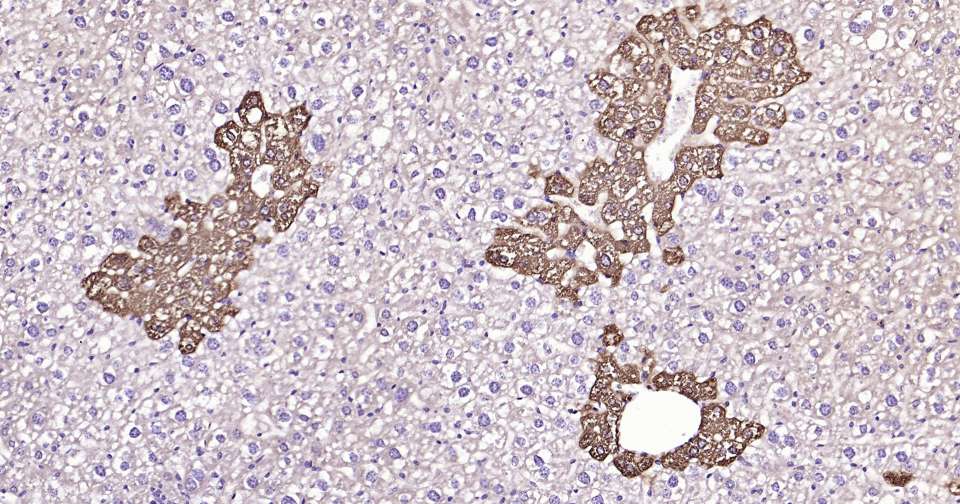

Immunohistochemical analysis of paraffin embedded human liver tissue slide using IHC0333 (Glutamine synthetase Kit).